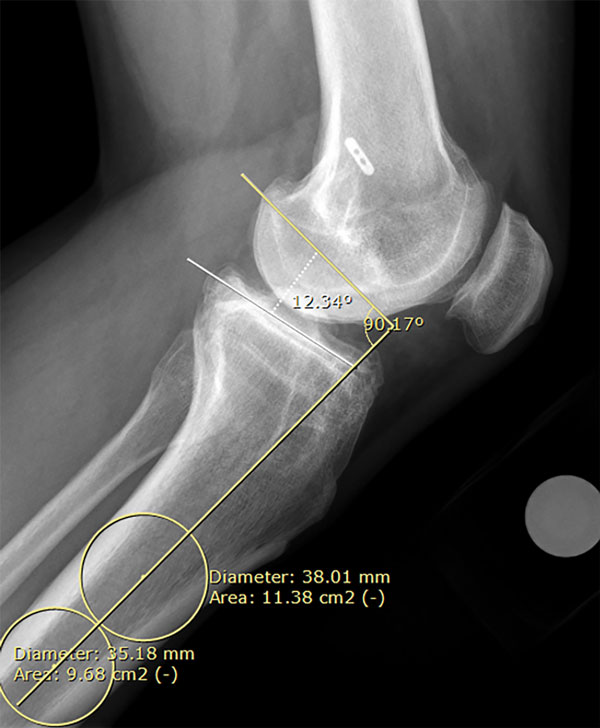

Es importante la medición del “slope” tibial, es decir, la inclinación del platillo tibial, no solo porque la osteotomía de apertura medial puede modificarlo, sino para definir si la osteotomía debe ser mono o biplanar, o bien, si se debe realizar una osteotomía deflexora asociada.9 El slope tibial se midió en la radiografía de perfil utilizando una línea mediodiafisaria a través del eje anatómico de la tibia y trazando una línea perpendicular a esta. Posteriormente se midió el ángulo formado por dicha línea perpendicular y otra que atraviesa el borde superior del platillo medial9 (fig. 2).

Figura 2: Medición de la inclinación posterior del platillo tibial.